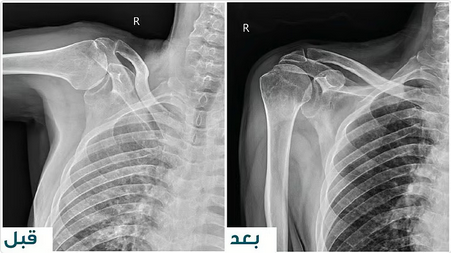

نجح فريق جراحة العظام في مستشفى المانع بالأحساء بقيادة الدكتور عدنان الراشد ، استشاري جراحة الأطراف العلوية والطب الرياضي وجراحة المفاصل الصناعية للركبة والفخذ في إجراء عملية استبدال مِفصل الكتف المقلوب لمريض سبعينيّ، عانى لفترةٍ طويلةٍ آلامًا حادةً وضعفًا شديدًا في الحركة؛ نتيجة إصابةٍ معقَّدةٍ في الكتف.

بدأت رحلة العلاج حينما راجع المريض عيادة جراحة الأطراف العلوية ، وأظهرت الفحوصات وجود تمزُّقٍ كاملٍ في جميع عضلات الكتف، وخشونةٍ شديدةٍ في المِفصَل؛ مما جعل التدخُّل الجراحيَّ الخيار الأفضل لضمان استعادة الوظيفة الحركية للمريض.

وبناءً على التقييم ، قرَّر الفريق الطبي إجراء عملية استبدال مِفصل الكتف المقلوب، وهي تقنيةٌ جراحيةٌ متقدِّمةٌ مصمَّمةٌ خصِّيصًا لعلاج الحالات التي تعاني تلف العضلات الدوّارة والخشونة المتقدِّمة في المِفصل.

وقد تمَّ تنفيذ العملية بنجاحٍ تامّ، وبدون أي مضاعفات ، وخضع بعدها إلى برنامج علاجٍ طبيعيٍّ مكثَّف لمدة ثلاثة أشهر، تحت إشراف فريقٍ متخصِّص في التأهيل الحركي.

بعد إنتهاء المريض من البرنامج، استعاد المريض كامل حركة الكتف دون ألمٍ أو أيِّ قيودٍ وظيفية؛ مما يعكس نجاح الجراحة والتأهيل الطبي المتطوِّر الذي حصل عليه.